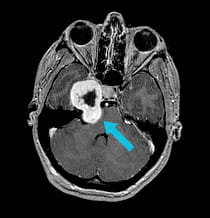

A 17-year-old girl came to the hospital with headaches after a fall. The CT scan and MRI showed a large trigeminal schwannoma at the base of the skull.

Pre-surgical scan shows large tumor at the base of the skull.

Scan after first surgical procedure shows front half of tumor has been removed using EEA surgery.

Scan after second surgical procedure shows complete tumor removal.

The tumor had two portions, separated by the petrous bone and the brain covering. The petrous bone contains many important structures, including critical cranial nerves and the carotid artery.

To avoid any damage to the nerves in and around the petrous bone and the carotid artery, the UPMC surgeons performed two separate surgeries from different angles to remove the trigeminal schwannoma.

Surgeons were able to completely remove the trigemina schwannoma. The girl temporarily had double vision that completely resolved over time, and some mild numbness related to the nerve from which the tumor originated.